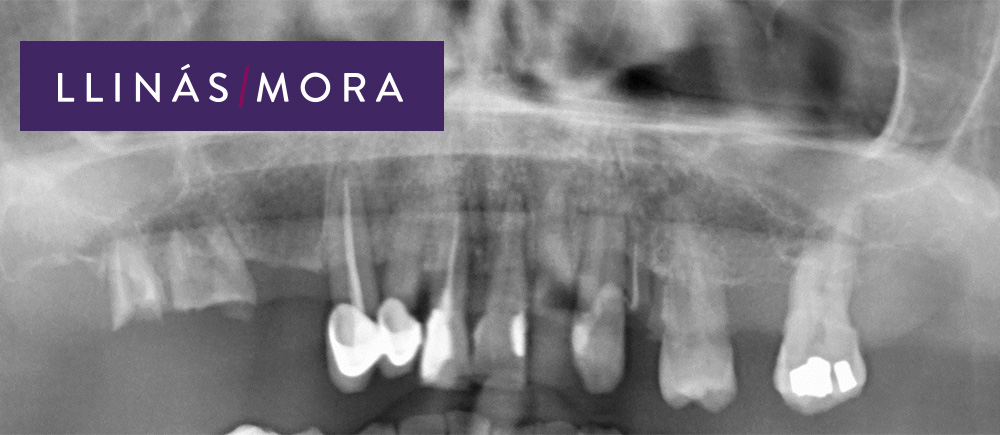

1. Paciente con enfermedad periodontal avanzada y perdida osea generalizada.

5. Ortofinal.